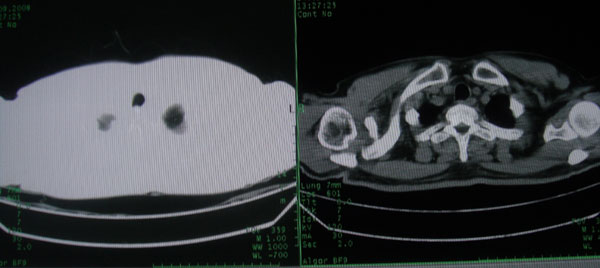

患者男性58岁因二周前起咳嗽,今天胸片示左上肺占位性病变行ct检查,无发热,无咯血痰.

左肺上叶病灶,实变但见含气支气管、空洞但未见壁内结节及积液;

考虑:①感染性病变(包括特殊感染型肺tb)

②肿瘤性病变(考虑患者年龄比较大的关系/所以不排除)

初学者。。。左肺空洞性病变,并可见阻塞性肺不张改变,鉴于患者为老年男性,且临床症状仅有咳嗽,全身中毒症状不明显,所以我首先考虑为左肺癌性空洞并左侧肺门淋巴结转移伴左肺阻塞性肺不张。结核性空洞放于第二位考虑,可以进行相关实验室检查。希望能有病理结果,谢谢!!!!!

左肺上叶实变影,内见支气管充气征及空洞影,病人年龄较大,无发热及结核中毒症状,心影左移,未见纵隔淋巴结肿大;不知实验室检查结果如何?有否嗜酸细胞增多,有没有进行治疗?就目前资料首先考虑1.感染性病变,2.慢性嗜酸性肺炎?可结合实验室检查并短期治疗复查,肺癌不能排除。